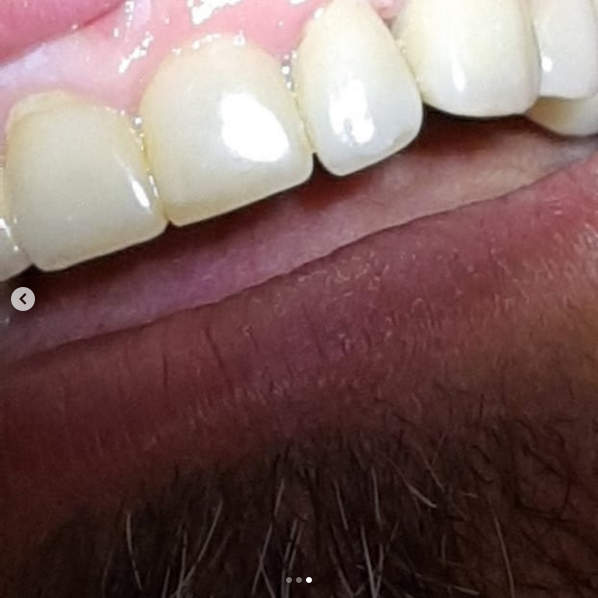

Фотографии до и после: Установка коронки на зуб

На странице представлено портфолио стоматологий Самары с фото работ до и после установки зубных коронок. Показываем, как можно полностью восстановить форму разрушенного зуба и эстетичный вид улыбки. На странице собраны разные клинические случаи восстановления одиночными коронками из металлокерамики, циркония или керамики. Изучите результаты до и после процедуры и выберите подходящую клинику для восстановления зуба в Самаре.

Установка металлокерамической коронки

Установка металлокерамической коронки

Установка металлокерамической коронки

Установка керамической коронки

Установка керамической коронки

Установка керамической коронки